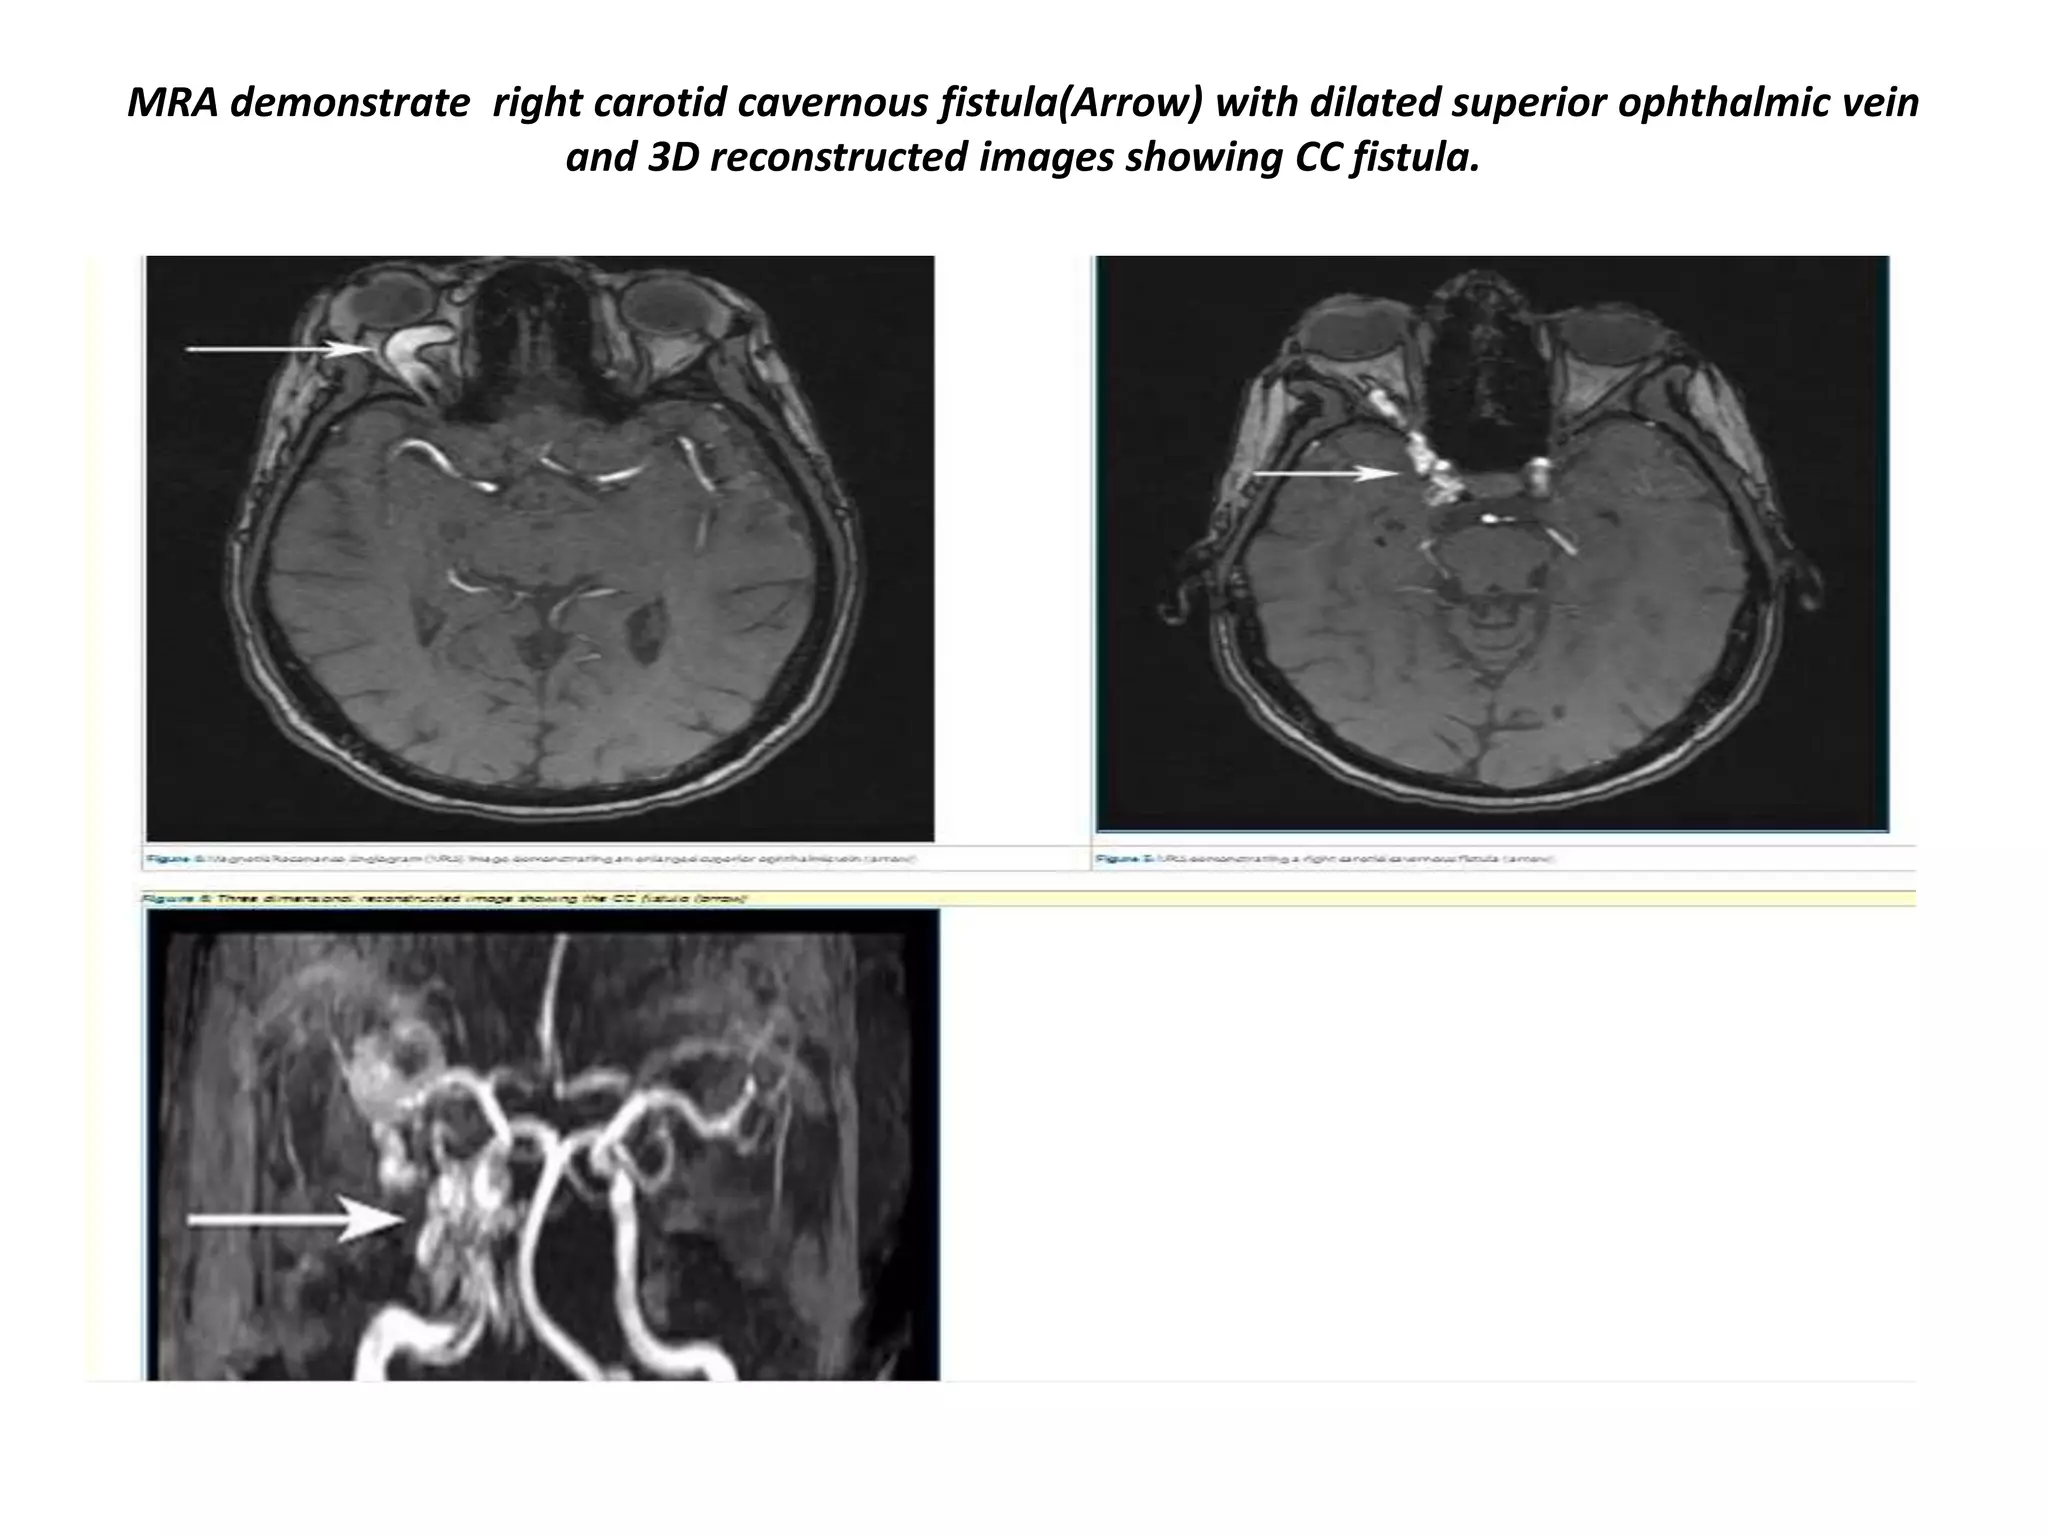

Carotid cavernous fistula in a 16years old boy presented with exophthalmous and objective tinnitus.

MRA demonstrate right carotid cavernous fistula(Arrow) with dilated superior ophthalmic vein

and 3D reconstructed images showing CC fistula.